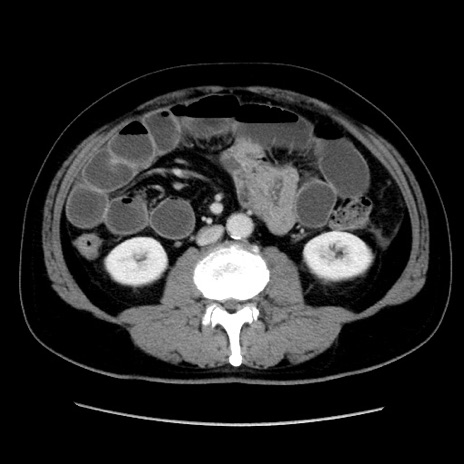

症例16(横断像)

冠状断像

【症例】 70歳代男性

【主訴】 腹痛、嘔吐

【現病歴】 約1ヶ月前より間欠的に腹痛と嘔吐あり、当院消化器内科を受診したところCTで多発する肝臓のLDAを指摘され、精査中であった。以降は消化器症状は安定していたが、2日前より嘔気と腹痛があり、同日より排便・排ガスが消失した。改善認めず、 本日、救急外来を受診した。

【既往歴】 大腸ポリープ切除後。

【身体所見】意識清明・会話良好、BT 36.3℃、BP 127/80mmHg、 P 80bpm、腹部:膨満あり、平坦・軟、上腹部正中および下腹部正中に圧痛あり、反跳痛なし、筋性防御なし。

【データ】WBC 7200、CRP 0.77